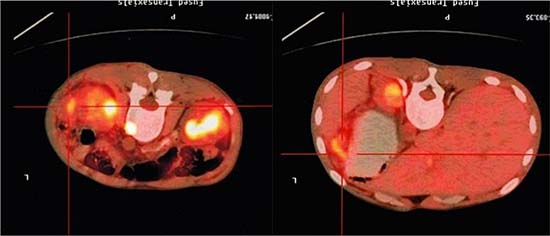

3 months after transplantation of preventive donor peripheral blood stem cells, 1 bag donor peripheral blood stem cells are infused and the mononuclear cell count reaches 0.2 × 108/kg. If disease recurrence appears or ETO fusion gene level increases, all the rests of the donor peripheral blood stem cells are infused. Then all patients show no symptom of GVHD or that of other complications. All patients are carried out with a follow-up visit after the transplantation, and the duration till the visit remains 27.5 months (18~54 months), the follow-up visit lasts till June, 2014. Under statistical survival situation, all cases occurred GVHD, 1 case of death due to complications, 4 cases of death due to relapse, the rest of the 10 cases are still disease-free survival (DFS), 2 years of disease-free survival rate was 66.7%, the longest disease-free survival time was up to 54 months. In accordance with the transplantation of patients with remission into relief groups (6 cases), and not ease group (9 cases), 2 years of disease-free survival rates were 66.7% and 66.7%. The survival curves of the two groups are equipped with no significant statistical significance(P > 0.05).There is 1 case of 4 months after transplantation in patients with medullary recurrence, infringement of eyes, shoulder and femur, line PET-CT examination more than in the whole body metabolism active mass lesion, consider to marrow granulocyte sarcoma, before mass located in the mediastinum, the lung, stomach, spleen, kidney and left along the greater curvature rectum, large green tumor cells, blood visible last multiple organ failure caused by outside pulp widespread violations of death as shown in Figure 5, survival curve as shown in Figures 6, and Figure 7.

Figure 5: PET-CT image of a patient (male, ETO+, AML) showing widespread violations of granulocytic sarcoma.